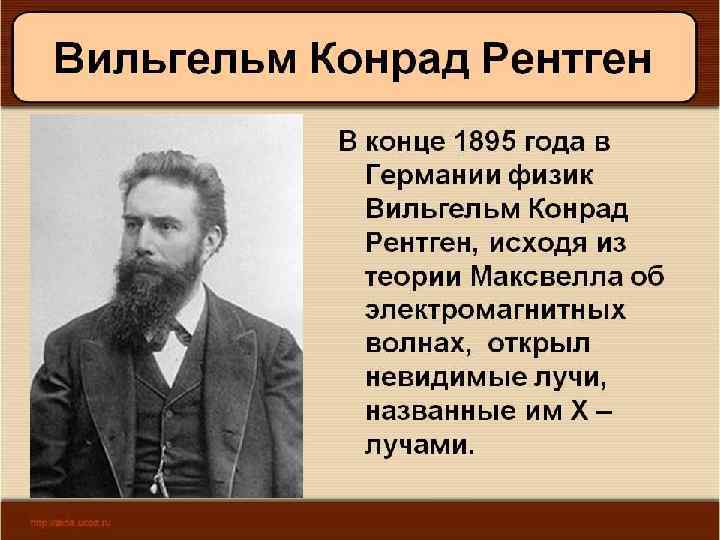

Германия, Бавария, Вюрцбюрг, музей Рентгена

Германия, Бавария, Вюрцбюрг, музей Рентгена